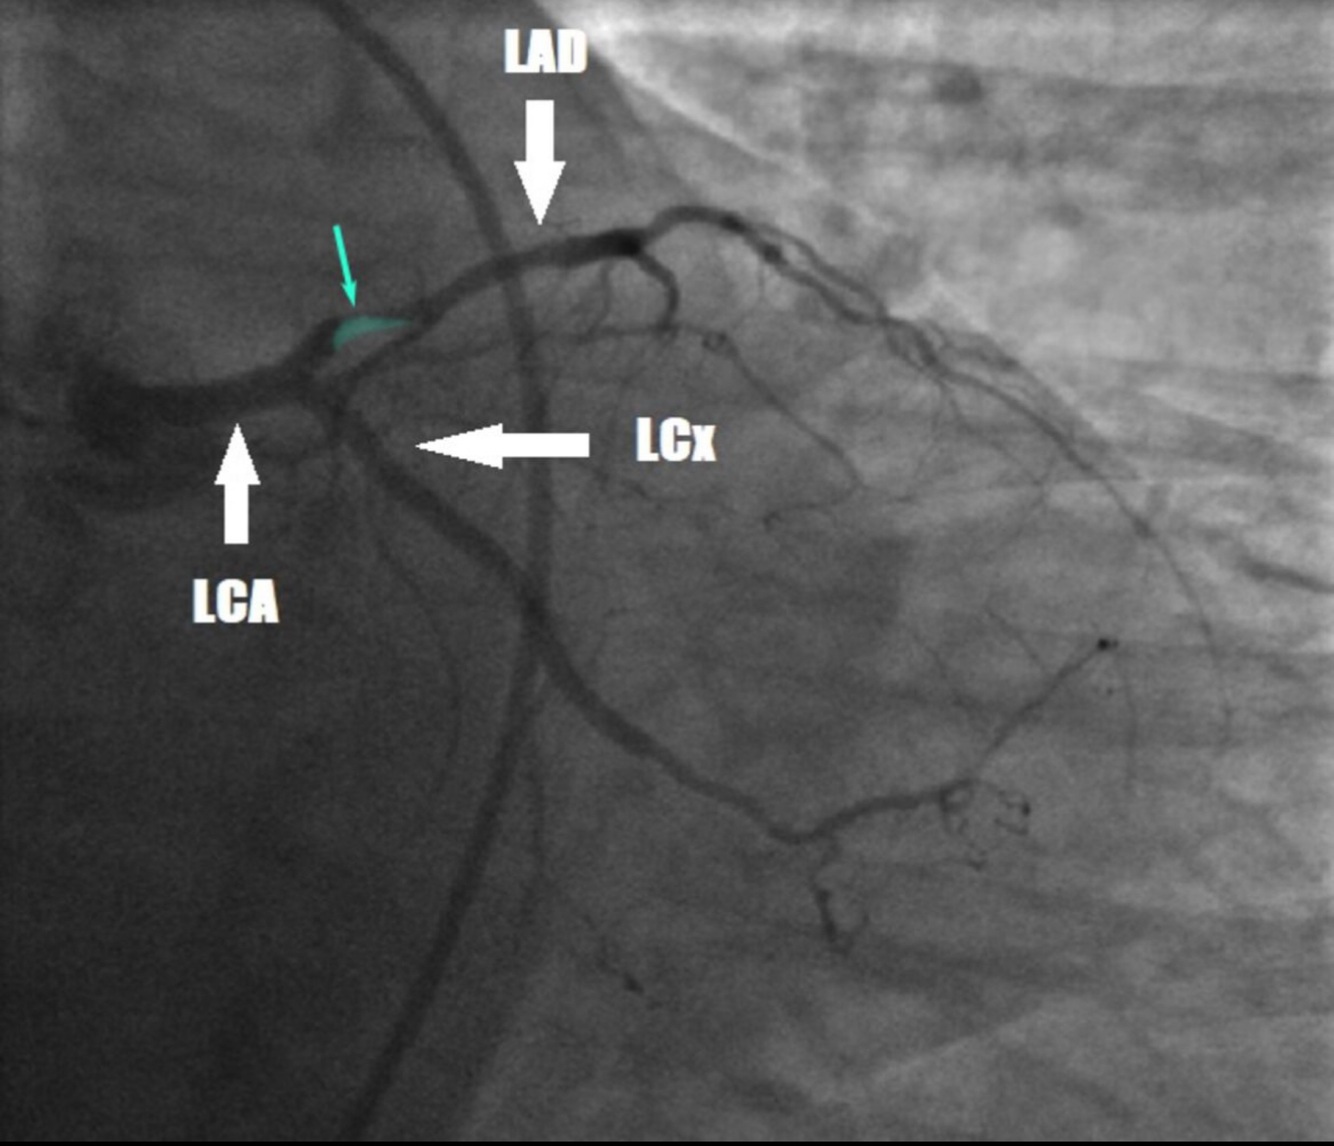

Una mujer de 54 años es llevada al departamento de emergencias debido a un historial de 2 horas de náuseas y dolor en el pecho retroesternal. Tiene un historial de 15 años de diabetes mellitus tipo 2. Sus medicamentos actuales incluyen atorvastatina, metformina y lisinopril. Ella es diaforética. Su nivel de troponina sérica es de 3,0 ng/mL (N: < 0,04). Se somete a un cateterismo cardíaco. Se muestra una fotografía de la angiografía coronaria realizada antes de la intervención coronaria percutánea. Un infarto agudo de miocardio asociado con el hallazgo de la angiografía es más probable que se manifieste con elevaciones de ST en cuál de las siguientes pistas en el ECG?

Las elevaciones de ST generalmente se desarrollan en los cables V1-V6 en el ECG como resultado de los infartos que involucran el LAD proximal. Los cables V1-V2 corresponden al territorio anteroseptal; los cables V3-V4 corresponden al territorio anterapical; los cables V5-V6 corresponden al territorio anterolateral. En algunos casos, también se pueden desarrollar elevaciones ST en los cables laterales (conductos I y aVL).